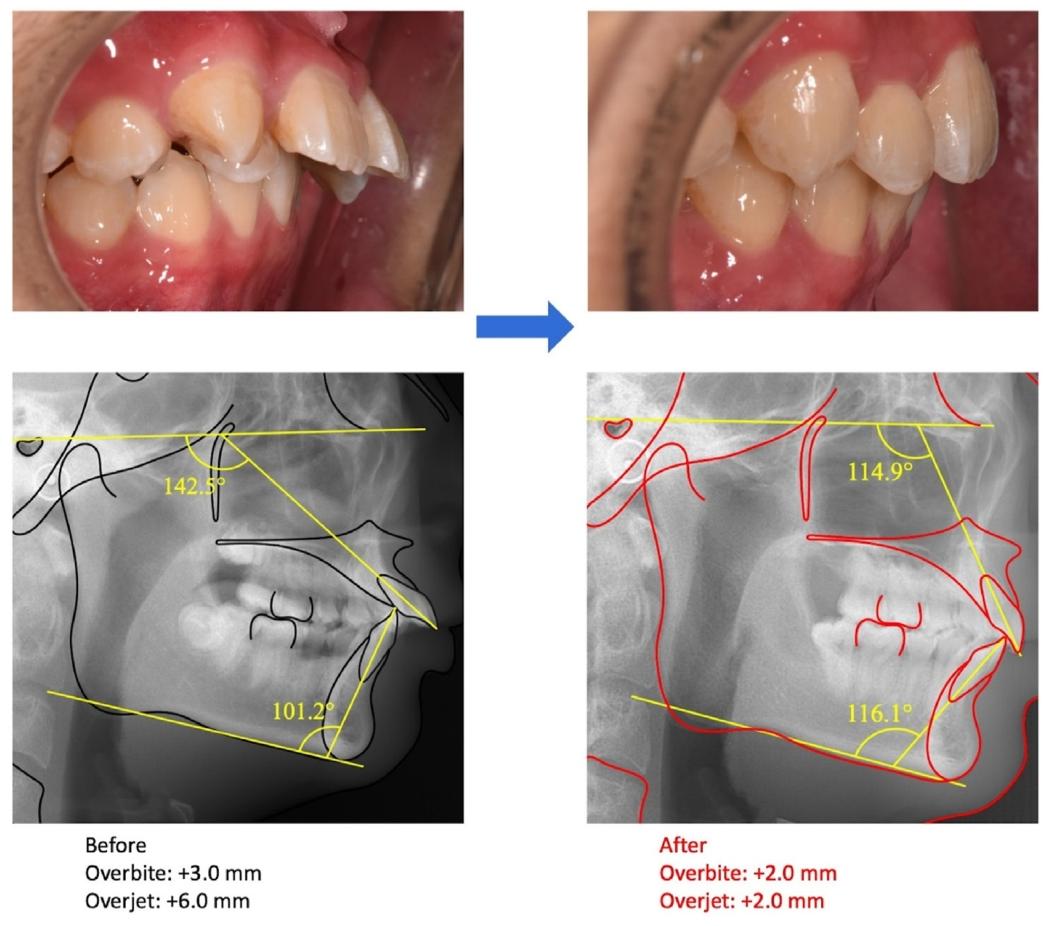

✅ 前牙覆盖从6mm降至2mm,覆合正常化

❸ 影像学验证

✅ 头影测量:上切牙唇倾度显著改善(U1-FH角从142.5°→114.9°),下颌逆时针旋转,骨性关系更协调